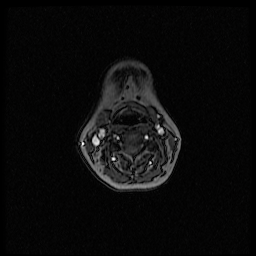

Could not get anybody to read the MRI today. Got pictures home, looked at them. One thing stands out to me. Here is the picture:

Here is the picture this thing doesn't want to work <http://i1131.photobucket.com/albums/m560/chicago-37/MR000005.png>

I cannot tell what the image provided anatomically is or what it means. Is it your neck? This particular view is very hard to decifer for someone who isn't medically trained.

Hello Chicago,

My daughter walked by here and said the bright white areas/spots on your MRI are your arteries..she works in the field...she could not see anything else outstanding...plus told me to stop( my family thinks I worry too much)......I have been reading you odd pain posts all along and feel as if you are me....I am hoping that all is well with you, as it seems it should be all things considered..

We will continue to browse and see what pops up...actually shortly after we posted that picture we realized that part of my chin is visualized as well as where the other components of the neck were.....this picture is pretty far from the areas on the bone scan that were bright.